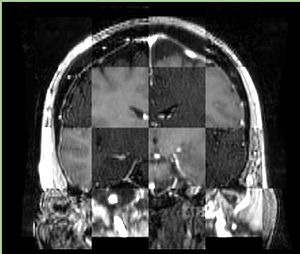

• Checkerboard appearance of unregistered images for the representative data of interest

• Case04